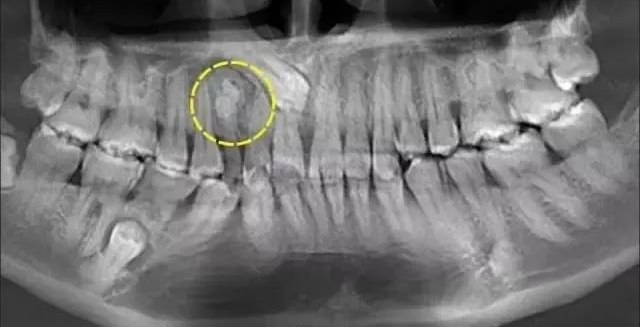

(1)多生牙的定位:

口腔ct怎么拍摄【专科天地】没有口腔CT,你根本不会想到自己的牙齿长得多“奇葩”!_https://www.jmylbn.com_新闻资讯_第14张